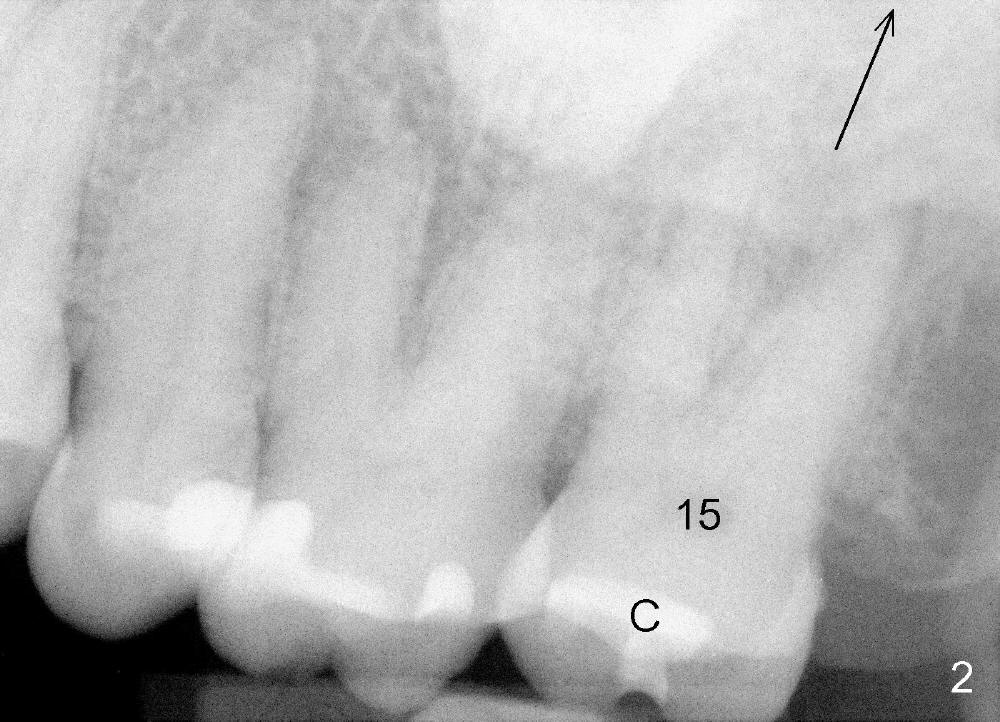

A 57-year-old lady presents for abscess buccal to the tooth #15 (Fig.1 A). Mesial and distal to the occlusal composite (Fig.2 C) is a crack line. In addition to long furcated roots, the upper border of the bone is not shown in this preop PA (arrow). Fig.3 is taken to show a thin septum surrounded by the mesiobuccal (MB), distobuccal (DB) and palatal (P) sockets (Fig.3). Osteotomy is initiated in the septum by 1.2 and 1.5 mm pilot drills, followed by 2,3,4 mm rounded tapered osteotomy at the depth of 17 mm. Nose blowing test is carried out after each step with negative result. Stability is achieved when a 4.5 mm tap is inserted at 17 mm, but the upper end of the tap is not visible (Fig.4,5). When a 5 mm tap is placed, stability is decreased, probably because the coronal end of the septum starts to break down (due to expansion). To re-gain stability, the 5 mm tap needs to go deeper. A 6 mm tap also achieves satisfactory stability at 20 mm. When the tap is removed, there is no air leakage. A 6x20 mm implant is placed with insertion torque > 60 Ncm; the upper end of the implant is still out of view in PA (Fig.6). Another problem is that the implant needs to go deeper to obtain sufficient occlusal clearance. The lower first molars and the 2nd premolars are missing. A panoramic X-ray has to be taken to show the apical end of the implant: ~ 3 mm into the sinus (Fig.7 ^). The maxillary tuberosity appears to grow downward (arrow). In other word, the tooth #15 appears to have been intruded due to overloading.